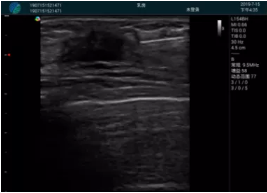

清晰顯示腺體內(nèi)低回聲快影,邊界清晰,包膜較光滑

確定進(jìn)針路徑并實(shí)時(shí)監(jiān)測(cè)抽吸針與腫塊位置關(guān)系

抽吸針進(jìn)入腫塊內(nèi)部進(jìn)行旋切

抽吸過(guò)程中可見(jiàn)腫塊明顯縮小,并根據(jù)腫塊位置改變針道位置

抽吸旋切后再進(jìn)行超聲復(fù)查,原腫塊區(qū)域未見(jiàn)殘留組織及出血